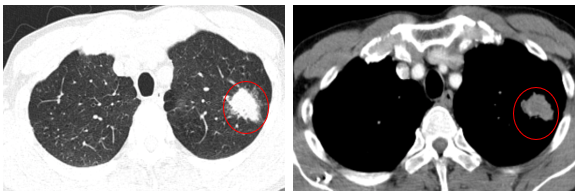

- Chụp cắt lớp vi tính lồng ngực (06/2025): Nhu mô đỉnh phổi trái có khối tổ chức kích thước ~35x25mm, bờ không đều, có cắt cụt một số nhánh phân thùy đỉnh, ngấm thuốc mạnh không đồng nhất sau tiêm. Thuỳ trên và dưới có nốt đặc nhỏ đường kính 2mm.

Hình 1:Nhu mô đỉnh phổi trái có khối tổ chức kích thước ~35x25mm,

bờ không đều, có cắt cụt một số nhánh phân thùy đỉnh, ngấm thuốc mạnh không đồng nhất sau tiêm